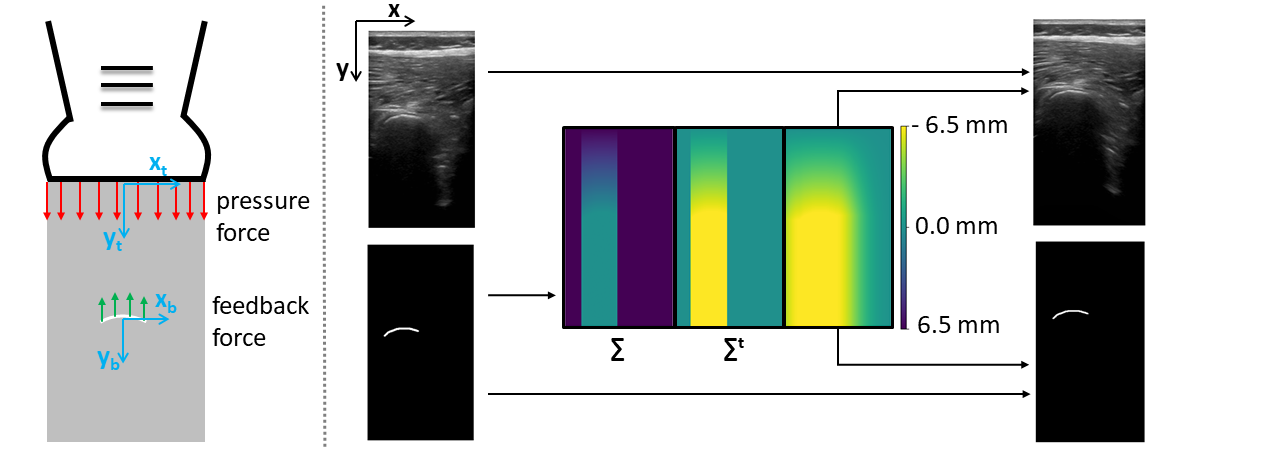

Figure 3: Deformation Pipeline: Left: The forces applied by the US probe (red arrows) and bones (green arrows), and the coordinate systems centered in the bone (xb,ybsubscript𝑥𝑏subscript𝑦𝑏x_{b},y_{b}) and the probe centroids (xp,ypsubscript𝑥𝑝subscript𝑦𝑝x_{p},y_{p}), respectively. Right: The original B-mode image and label. The label is used to compute the DF (ΣΣ\Sigma) induced by the probe pressure. To avoid unrealistic gap above the skin layer, the DF is expressed in the probe coordinate system (ΣtsuperscriptΣ𝑡\Sigma^{t}) and blurred. ΣtsuperscriptΣ𝑡\Sigma^{t} is finally applied to both image and label.

2.1 Deformation

In this section, we propose a deformation model, seen in Fig. 3 that simulates deformations from variations in the contact pressure of the US probe on interrogated tissues. Assuming a transducer displacement dprobesubscript𝑑probed_{\text{probe}} for a given augmentation, we derive its respective Displacement Field (DF) for the deformed medium. This DF is then applied to the input B-mode image resulting in our proposed augmentation. The DF is generated from a simplified physical model of the interactions of soft tissues, bones and the transducer. Specifically, we assume that soft-tissues are isotropic and homogeneous, that the probe pressure is applied along the axial direction and that the bone is a static body without deformation or transformation. Furthermore, we assume that only tissues between the probe and bone undergo compression and lateral tissue deformation is negligible. In lateral tissues there is no deformation, thus the DF is constant and equal to dprobesubscript𝑑probed_{\text{probe}}. In tissues laying between bone and probe, we can derive the deformation components as ϵyy=F/EAsubscriptitalic-ϵ𝑦𝑦𝐹𝐸𝐴\epsilon_{yy}=F/EA, where A𝐴A is the transducer area and F𝐹F is the force applied by the probe and E𝐸E is the Young’s Modulus. This can be rewritten as F=dprobeEA/yprobe𝐹subscript𝑑probe𝐸𝐴subscript𝑦probeF=d_{\text{probe}}EA/y_{\text{probe}}, where yprobesubscript𝑦probey_{\text{probe}} is the position of the probe in the bone coordinate system. Hence, we have:

In order to avoid unrealistic gaps between skin and transducer, we rewrite the displacements in the transducer coordinate system. In this coordinate system ybonesubscript𝑦boney_{\text{bone}} is the position of the bone with respect to the probe. This corresponds to applying an offset of dprobesubscript𝑑probed_{\text{probe}} to the DF equation. To ensure smooth transitions between regions with large and small displacements, we add lateral gaussian smoothing. The transducer translation dprobesubscript𝑑probed_{\text{probe}} is randomly sampled in our US augmentation. Pseudo-code is shown in Algorithm 1.